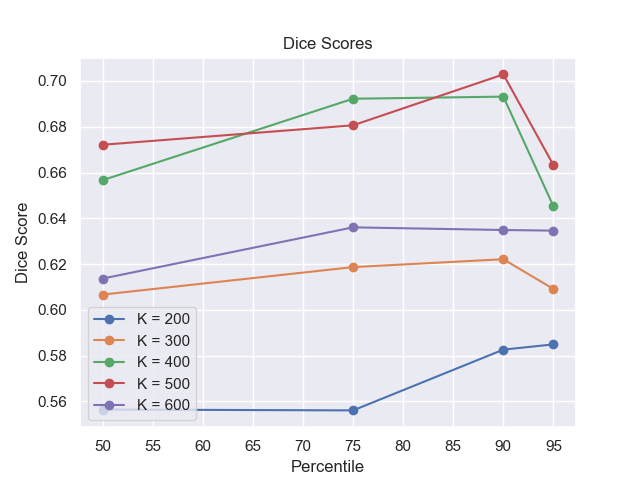

In Figure 5 we plot the dice scores obtained for different values of these hyperparameters. As we can observe, we obtain the best performance when employing 500 noising steps and selecting the pixels in the percentile of the saliency maps. In Figure 7 we display counterfactuals obtained with different noise levels. We can observe how smaller values of the noise parameter don’t allow the diffusion model to modify the image to an adequate degree, while bigger values introduce artifacts that impact the image quality of the generated image, consequently also hurting the dice score of the corresponding anomaly map.